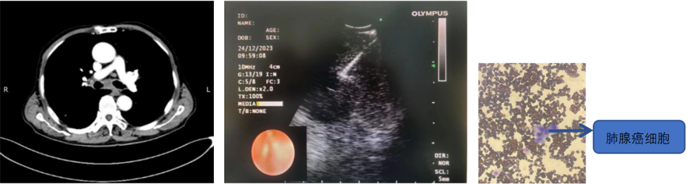

病例2

患者,男,70歲,近2個月來“活動后呼吸困難,近日又出現(xiàn)痰中帶鮮血”,收住院。胸部增強CT見“左肺下葉外周型占位,肺門、縱膈淋巴結腫大”。張強主任帶領團隊討論分析患者病情,高度懷疑為腫瘤性病變,且普通電子支氣管鏡獲取組織困難,病變緊貼主動脈,經(jīng)皮肺穿刺活檢風險大。為明確診斷及分期,決定為患者實施支氣管內超聲引導下針吸活檢術(EBUS-TBNA)+電子支氣管鏡下病灶活檢+現(xiàn)場快速評價(ROSE)。術中ROSE快速診斷查找到肺腺癌細胞,手術過程順利。最后病理檢查明確診斷為肺腺癌,為患者的下一步治療確定了方向。